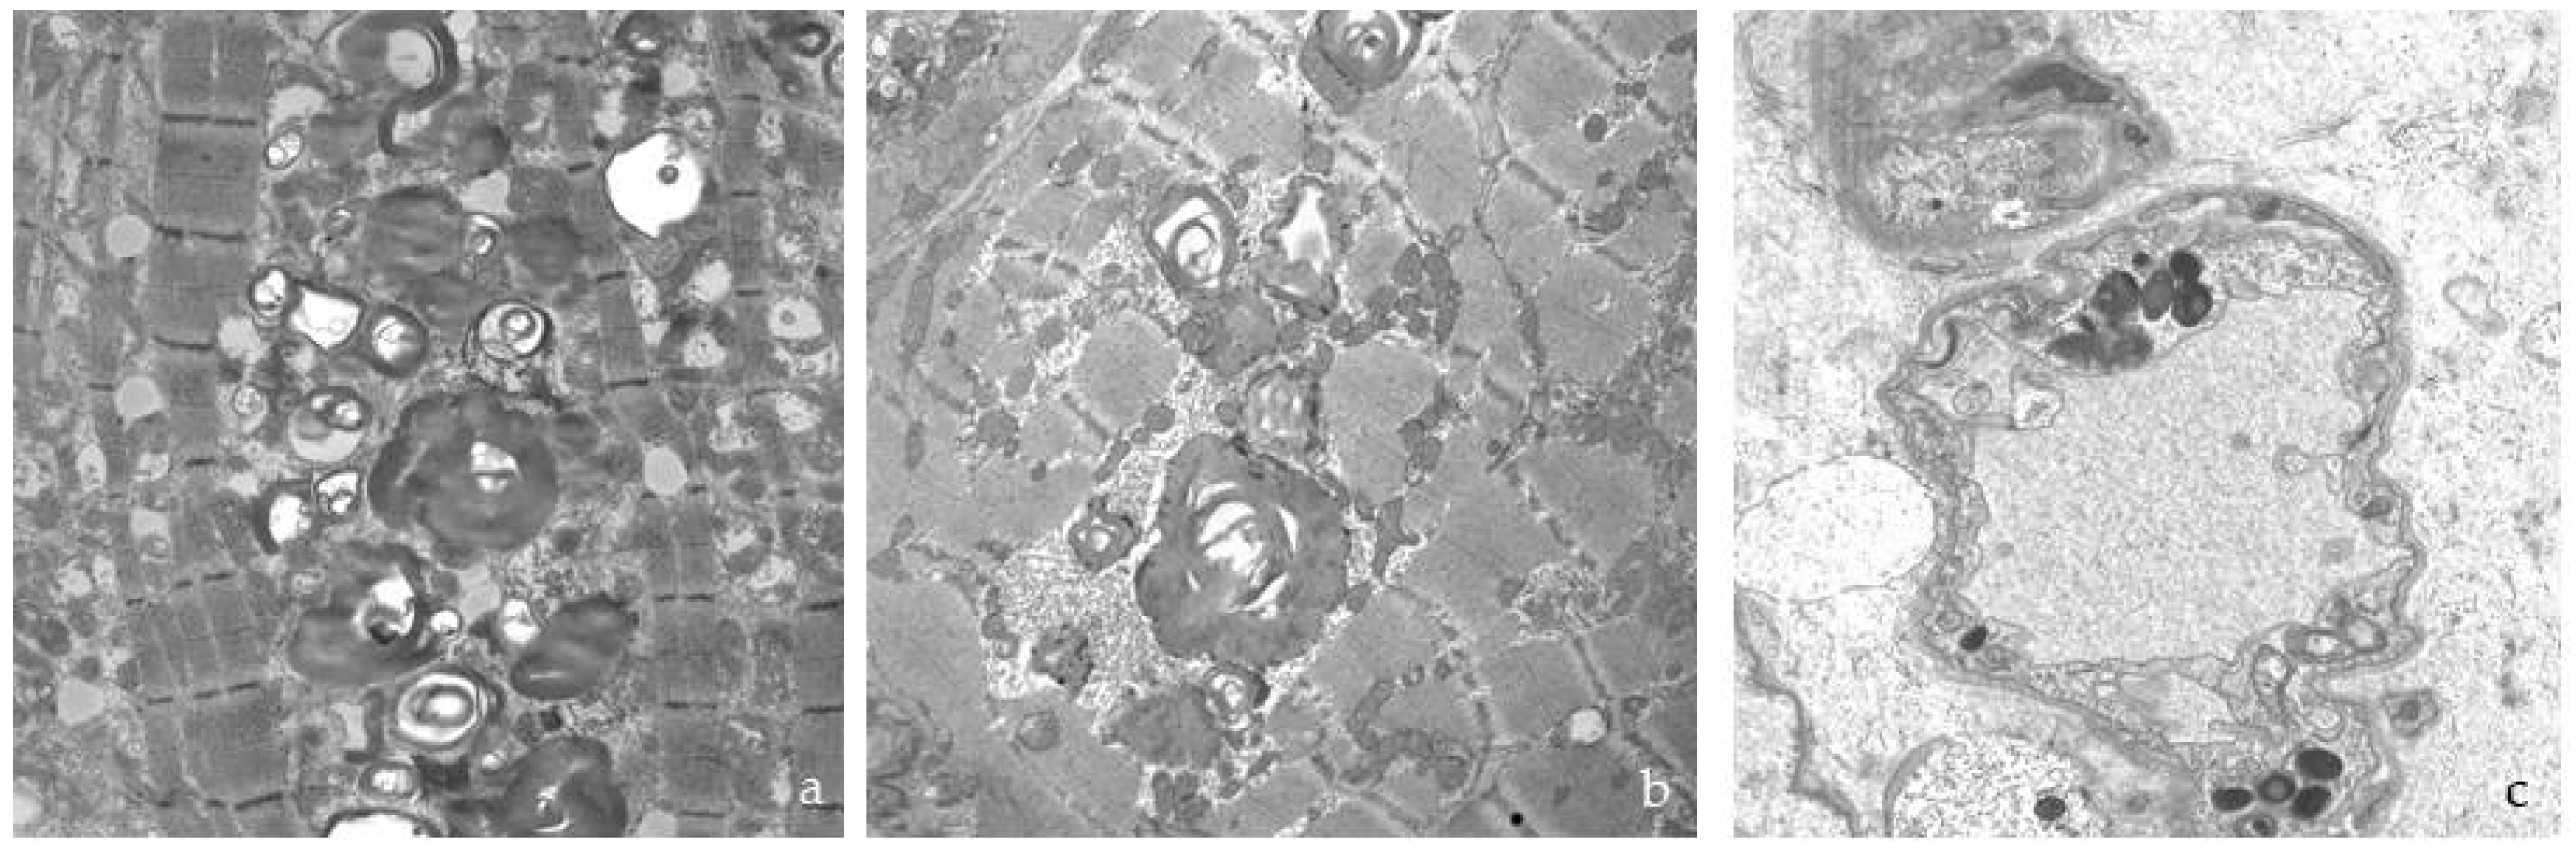

3.3. Histological and Ultrastructural Study